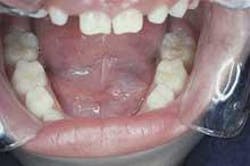

Intraoral examination revealed a well-defined, bluish dome-shaped swelling on the floor of the mouth (see photo). The lesion measured approximately 25mm in diameter and did not cross the midline. Palpation revealed a soft, fluctuant mass. No other soft tissue abnormalities were noted.